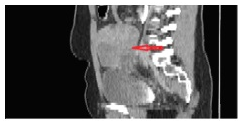

The CT (Figures 2–4) showed a large, multi-spaced, clearly defined circumscribed mass composed of cystic and solid components with a volume of 400milliliters (maximum diameter: 10.8cm).The mass extended up to the level of the right distal ureter without infiltrating it. Normal lymph nodes (para-aortic space) were noted. No other pathological findings were detected in the abdomen.

Figure 4 CT abdomen (sagittal plane) shows the cyst presence in the right ovary (10.5cm×7cm) with solid and cystic elements. The red arrow indicates the lesion.